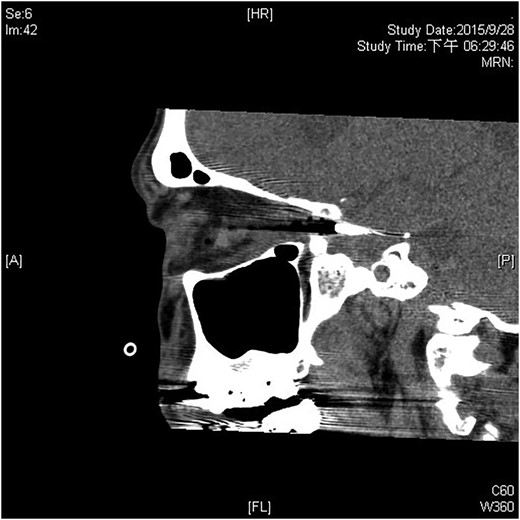

A 60-year-old man was admitted to our medical ward due to aspiration pneumonia. He had a medical history of diabetes mellitus, end-stage renal disease; a tuberculosis bacilli-related thoracic spine infection with paraplegia, and a previous coronary artery bypass graft. During his third day at the hospital, he obtained a ballpoint pen and inserted it into his left eye. On physical examination, the patient appeared to be alert with normal vital signs. The ballpoint pen protruded from his left upper eyelid; it was firmly lodged in his left medial orbit between the globe and nose, causing left eye proptosis (Fig. 1). Neurologic examinations revealed that the patient was neurologically intact except for complete left ophthalmoplegia. Brain CT scanning revealed a tubular foreign body that was located in the anteroposterior plane extending from the orbital apex and directly into the parasellar region (Fig. 2). The metallic portion of the foreign body was entrapped in left optic canal (Fig. 3). There was no evidence of intracranial hemorrhaging or a rupture in the globe (Fig. 4). The patient was treated with high-dose steroids to protect the optic nerve. The plastic ballpoint pen and metallic tip was withdrawn from the orbit smoothly at bedside, and no craniotomy was required. The ballpoint pen had been inserted to an estimated depth of 7 cm through the eyelid and into the orbit. The patient was then transferred to the ICU for close neuro-observation. We initiated intravenous broad-spectrum antimicrobials and vancomycin therapy and continued these medications for three weeks. A psychiatrist was consulted for a complete psychiatric evaluation and suicide prevention. The follow-up CT scan showed no retained foreign bodies or intracranial hemorrhaging (Fig. 5). At the last follow-up examination 2 months after the injury, the patient presented with complete left ophthalmoplegia and blepharoptosis but intact visual function.

The ballpoint pen tip reaches into the parasellar region via the optic canal.